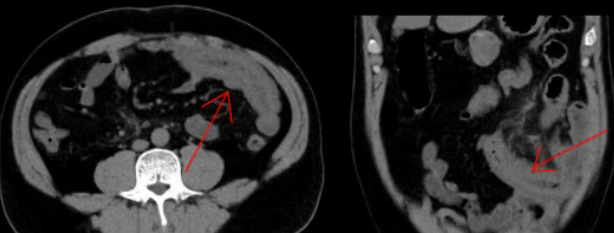

这种疾病疝环位于腹腔内部,体表无法触及,肠管一旦嵌顿,数小时内就可能血供中断,引发肠坏死,而腹部术后孔隙、肠粘连正是主要诱因。医生深知每延误一分钟,患者就多一分危险,当即开具CT检查单,吩咐护士同步建立静脉通路、抽血化验。

看着家属攥着检查单发抖的手,医生轻声安抚:“别慌,交给我。”CT结果确诊腹内疝、小肠嵌顿,高度怀疑肠坏死,当即决定:“马上住院,准备手术!”面对家属的恐慌,急诊医生耐心告知:“情况虽险,但发现及时,需要立刻手术,请相信我们。”护士推着平车将张大叔送往手术室。随着平车远去,急诊医生转身回到诊室,又一位患者被搀扶进来,他随即投入新的坚守。